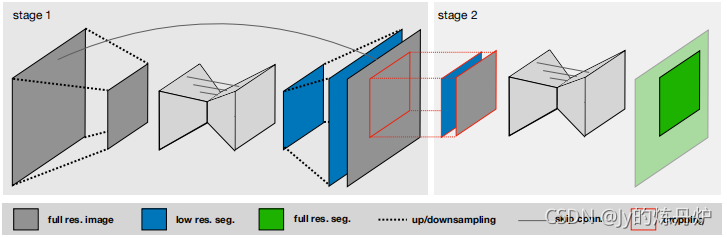

模型提供了三种Unet架构:2D U-Net, 3D U-Net and a U-Net Cascade(U-Net级联)。三者特点如下:

- Unet Cascade首先用低分辨率图像粗分割,再用全分辨率图像细分割。

2.4 U-Net Cascade

首先要对降采样的图像进行3D U-Net训练(阶段1)。然后,将阶段1结果上采样到原始尺寸,作为附加输入通道传递到第二个3D U-Net,第二个3D U-Net在上以全分辨率进行训练(第2阶段)。